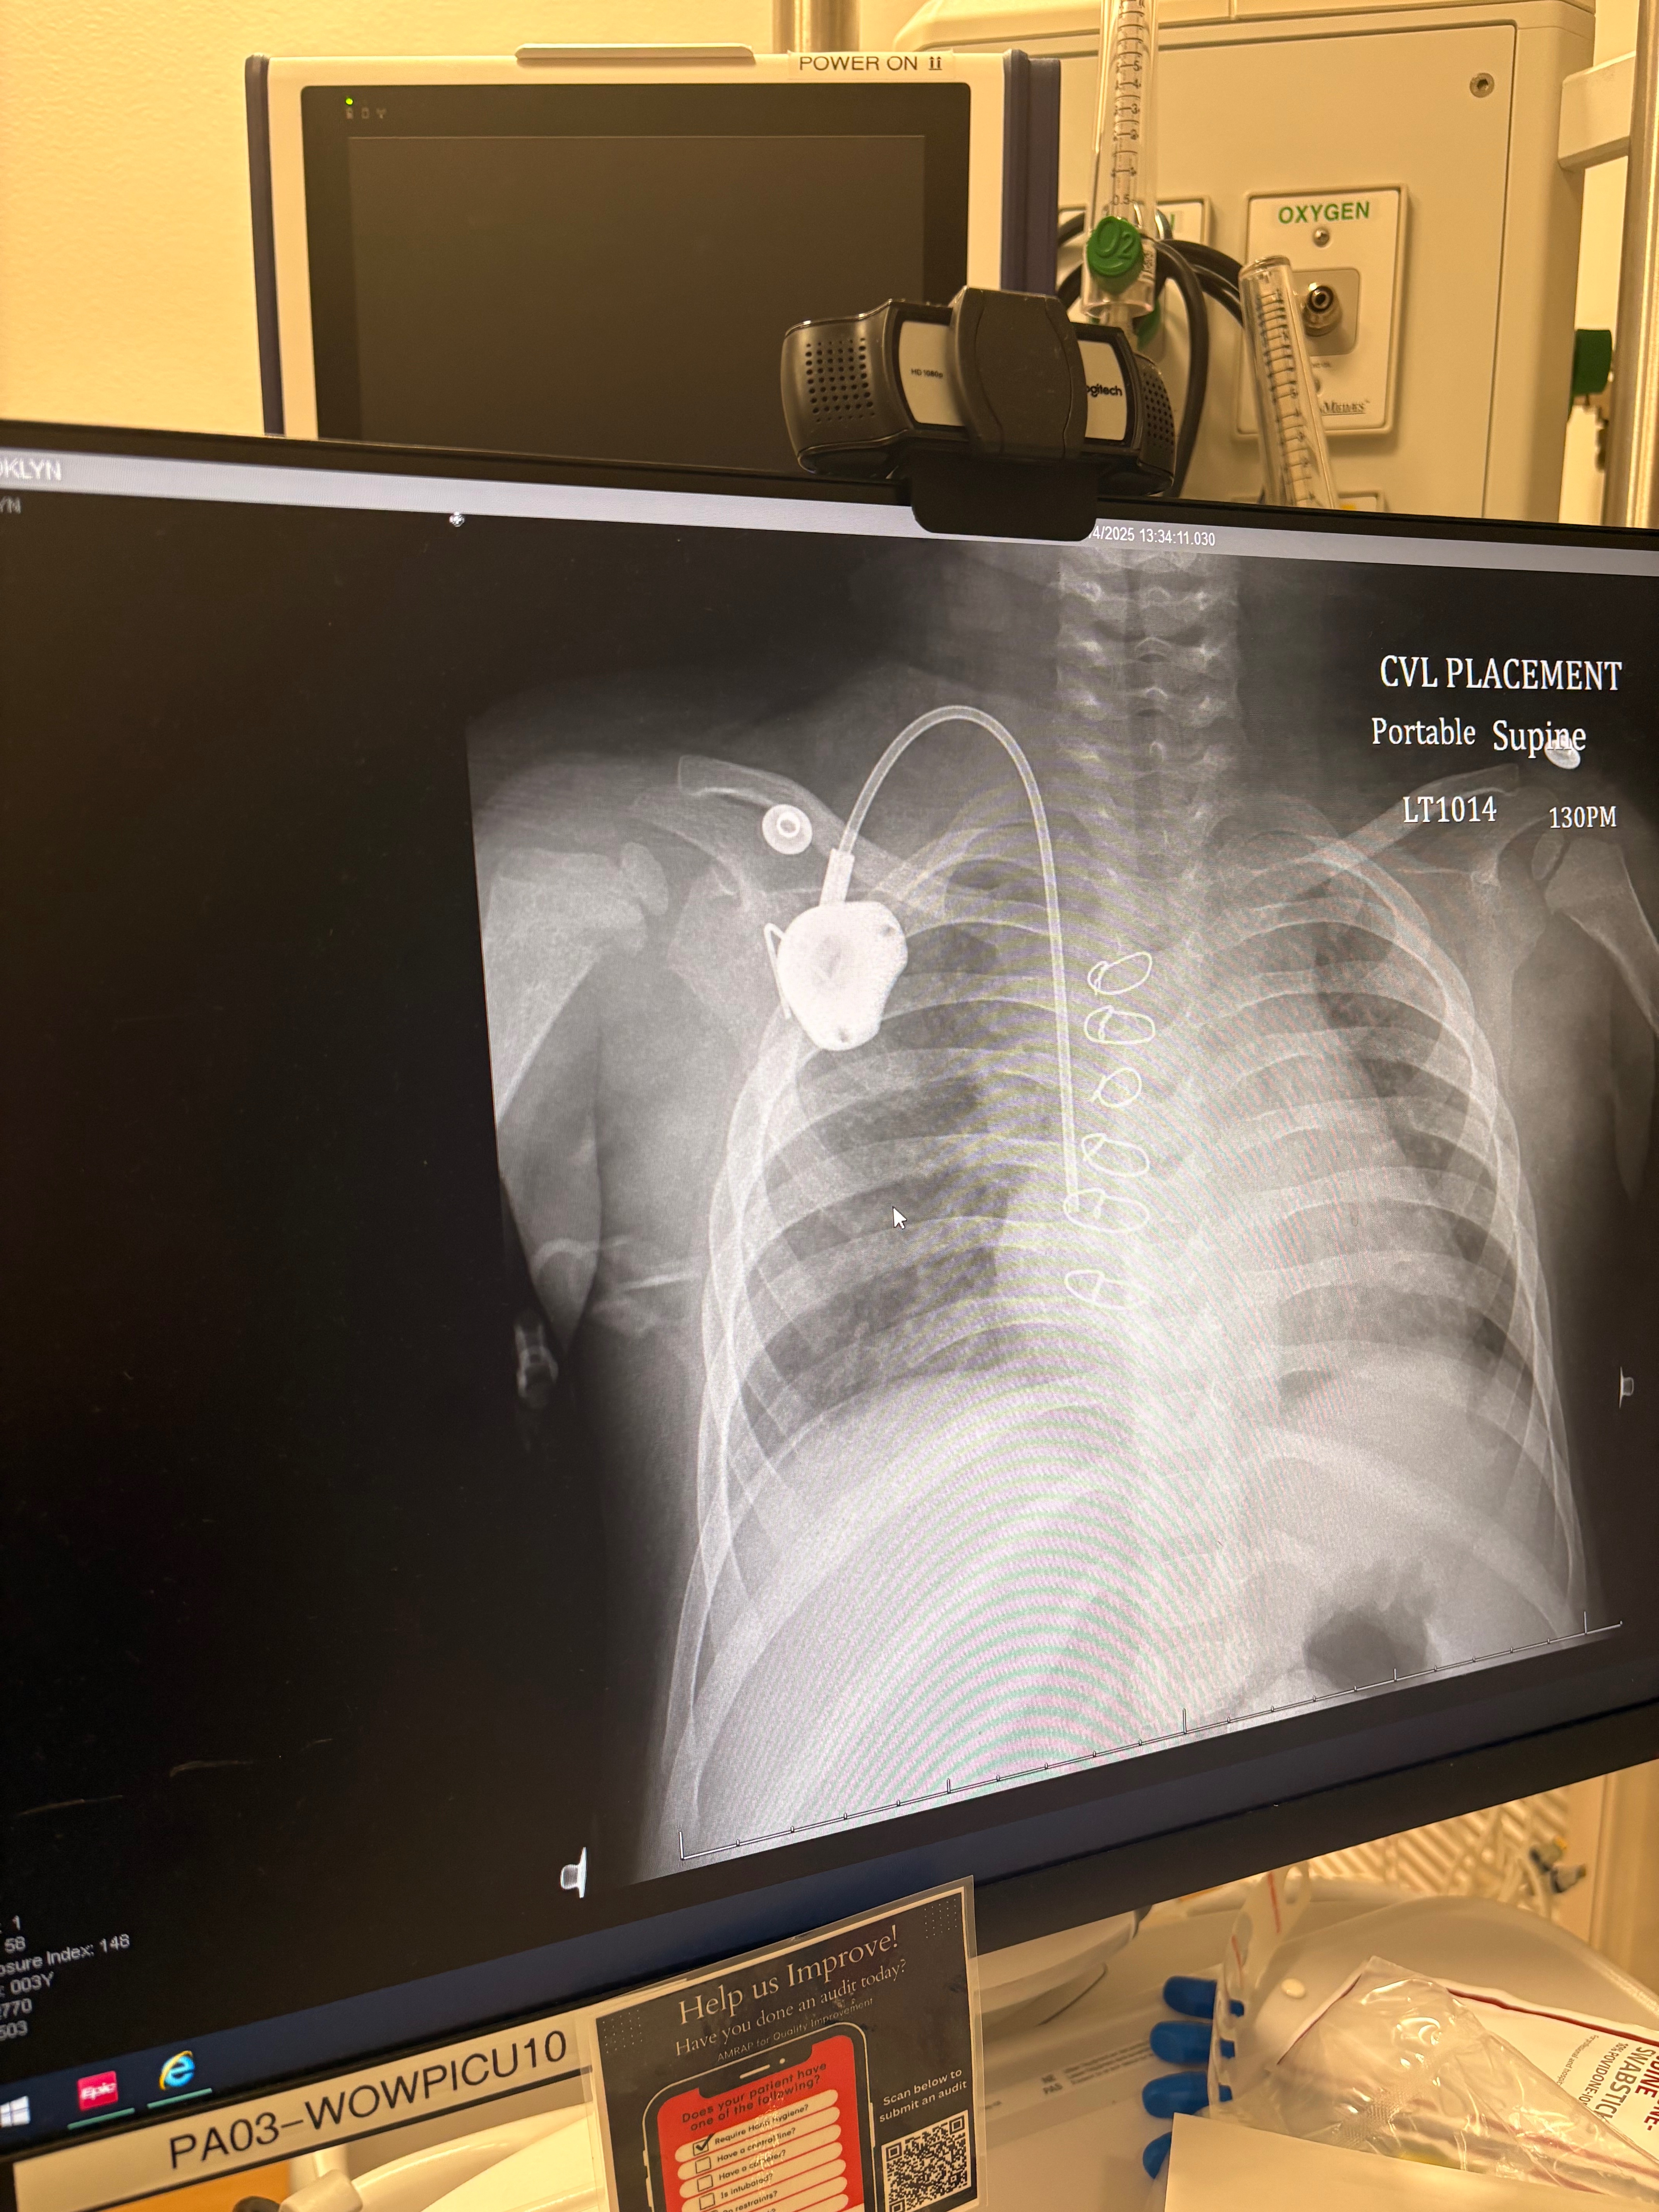

My beautiful, brave girl, who has already endured so much, is now facing a new and terrifying battle. We are currently 15 days into what will be a 37-day hospital stay. She has already undergone six rounds of chemotherapy, three platelet transfusions, three blood transfusions, and two lumbar punctures. She had surgery to place a port in her chest and will continue with regular LP procedures to monitor her bone marrow and administer one of her three chemo’s directly into her spine. BK is just three years old.